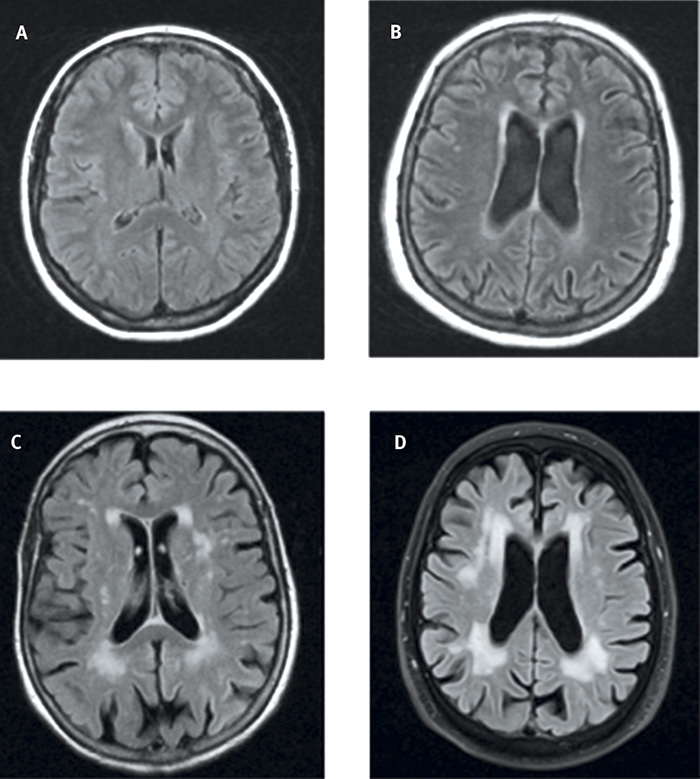

Förändringar i vit substans (Fazekas skala). Av flera publicerade skalor för visuell gradering av förändringar i vit substans i hjärnan är en modifierad version av Fazekas ursprungliga skala enklast [20], varför vi rekommenderar den för klinisk bedömning vid DT och MRT. Grad 0 har ingen eller enstaka punktformig förändring i vit substans och grad 1 har multipla punktformade förändringar i vit substans, som kan ses i alla åldrar och är vanliga hos patienter äldre än 65 år. Förekomst av ett litet antal sådana förändringar saknar oftast klinisk betydelse. Grad 2 innebär begynnande sammanflytning (konfluens) av punktformade förändringar och grad 3 konfluerande förändringar. Grad 2 betraktas som patologiskt hos patienter yngre än ca 70 år medan grad 3 alltid är patologiskt (Figur 4).

Figur 4. Förändringar i vit substans: grad 0 (A), grad 1 (B), grad 2 (C) och grad 3 (D) enligt modifierad Fazekas skala.